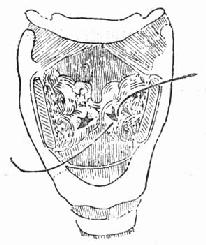

(1)急性声门上损伤:声门上损伤包括甲状软骨板上半部骨折和会厌损伤(图96-1)。有急性喉阻塞者首先行常规气管切开术,然后行前连合直接喉镜检查,注意喉水肿和喉及下咽粘膜裂伤的情况。手术包括缝合粘膜裂口并切除会厌及会厌谿之血肿组织,颈前在舌骨水平做横切口,剪断舌骨后,给行切开甲舌膜进入咽腔(图96-2)。切除会厌,会厌根部血肿组织及双侧假声带(图96-3)。用丝线缝合喉粘膜,尽量对合复位骨折的甲状软骨板,并用丝线缝合甲状软骨外板软骨膜,再缝合甲舌膜(图96-4)。逐层缝合切口。术后48h经鼻咽置入下咽部一条吸引引流管,持续引流。待喉部手术后反应消退,可试行堵管,呼吸道通畅即可拔除气管套管。

图96-1 声门上损伤

图96-2 声门上损伤手术方法 剪断舌骨,纵行切开甲舌膜。